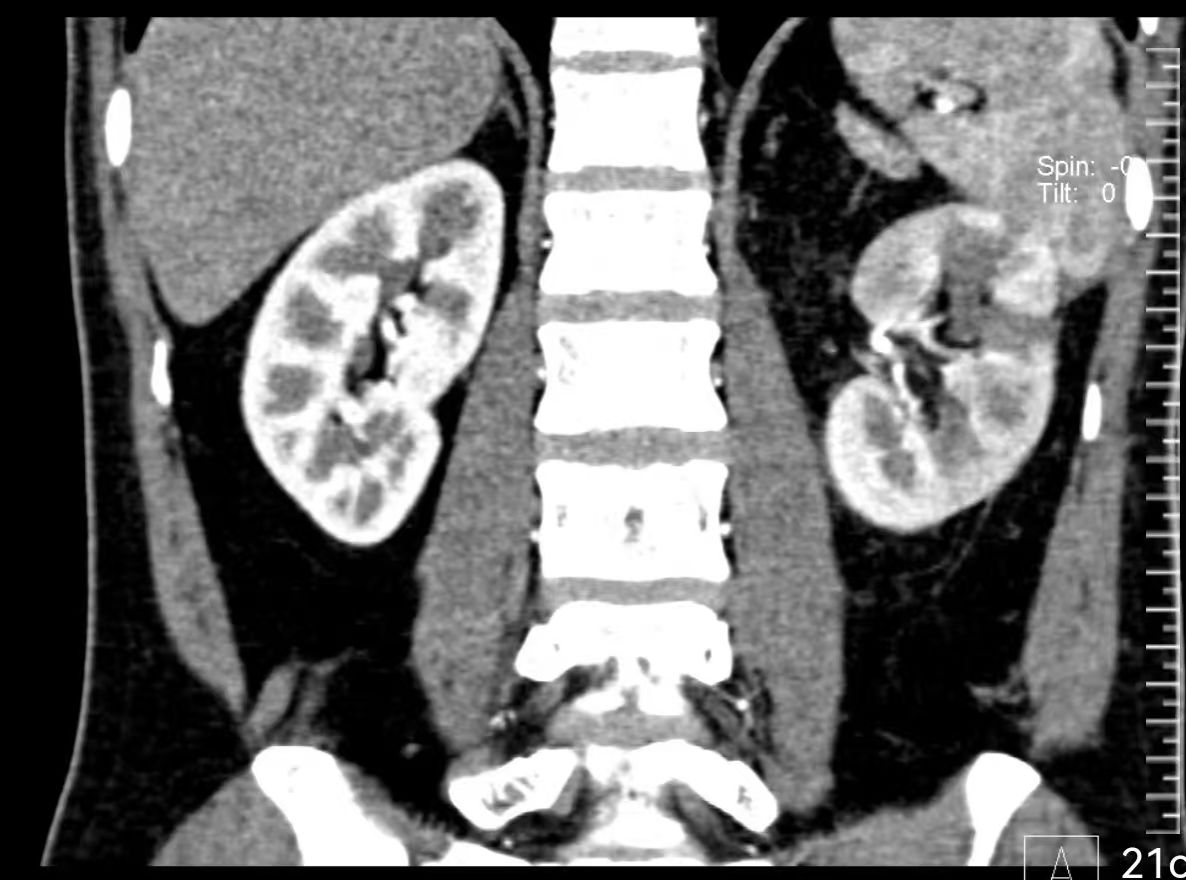

术后病理证实为肾透明细胞癌,且切缘为阴性,意味着肿瘤被彻底根除。更令人欣喜的是,术后4周复查显示,文先生左肾的肾小球滤过率保留在28ml/min,这意味着有高达51%的左肾功能被成功保留了下来!他术后第一天即可下床活动,恢复迅速,目前已顺利出院。这次手术完美达成了国际公认的保肾手术“三连胜”目标:肿瘤切净、肾功能最大程度保留、无严重并发症。

(术后4周复查CT显示肿瘤已被完整切除)

(肾脏形态得到最大限度的保留)